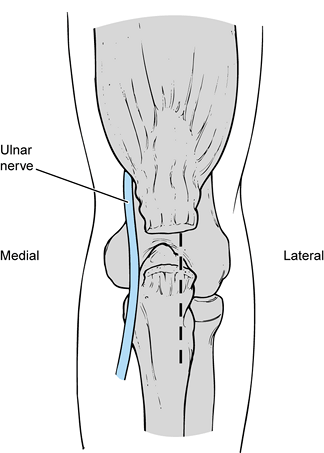

the ulnar nerve was always transferred anteriorly in association with

an ulnar collateral ligament reconstruction. It has been shown,

however, that there is an increased complication rate with

transposition of the ulnar nerve, and therefore I now transfer the

nerve only when clinically indicated. When the patient does not have

chronic ulnar nerve symptoms, leave the ulnar nerve within the cubital

tunnel. This requires a change in the technique for transfixing the

ulnar collateral ligament graft proximally at the medial humerus. When

the patient has clinically significant ulnar neuritis, transfer the

ulnar nerve anteriorly in a submuscular fashion in conjunction with the

ulnar collateral ligament reconstruction.